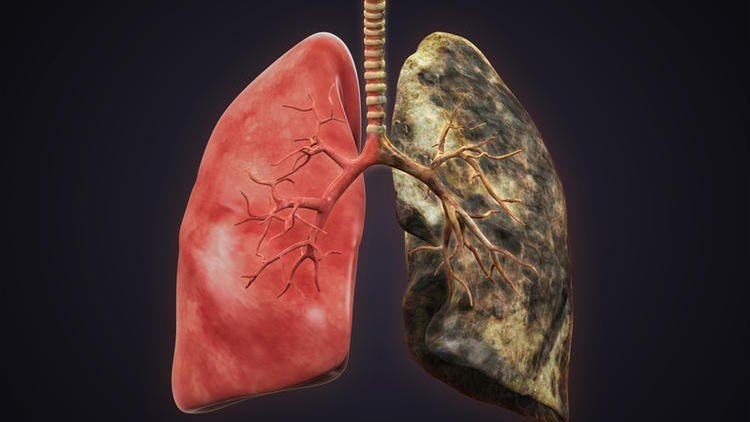

Рентген легких при онкологическом заболевании не всегда оказывается информативным, то есть способен демонстрировать затемнение или просветление. Кроме того, первая степень патологии также определяется далеко не всегда, за счет незначительных размеров новообразования до 5 мм. Несмотря на это, рентгенография является одним из самых достоверных методов диагностики рака на любой стадии. Для того чтобы результаты оказались максимально достоверными, рекомендуется осуществлять исследование не только в прямой, но и в боковой проекции.